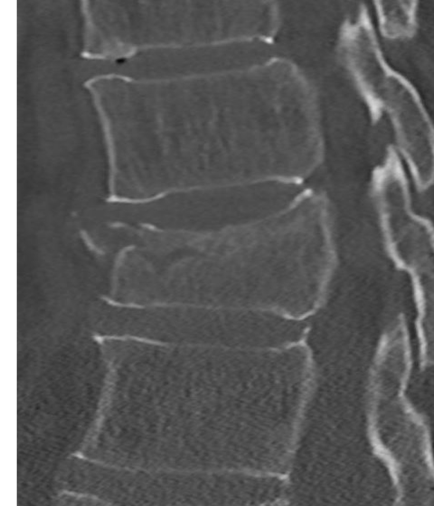

Stabiele of instabiele wervelbreuk

Bij een stabiele wervelbreuk is alleen het wervellichaam gebroken. Als een breuk stabiel is kan het wervellichaam niet verschuiven, waardoor het ruggenmerg niet beschadigd kan raken. Een operatie is dan niet nodig.